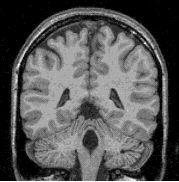

A result example:

classification (grey=100,white=200)